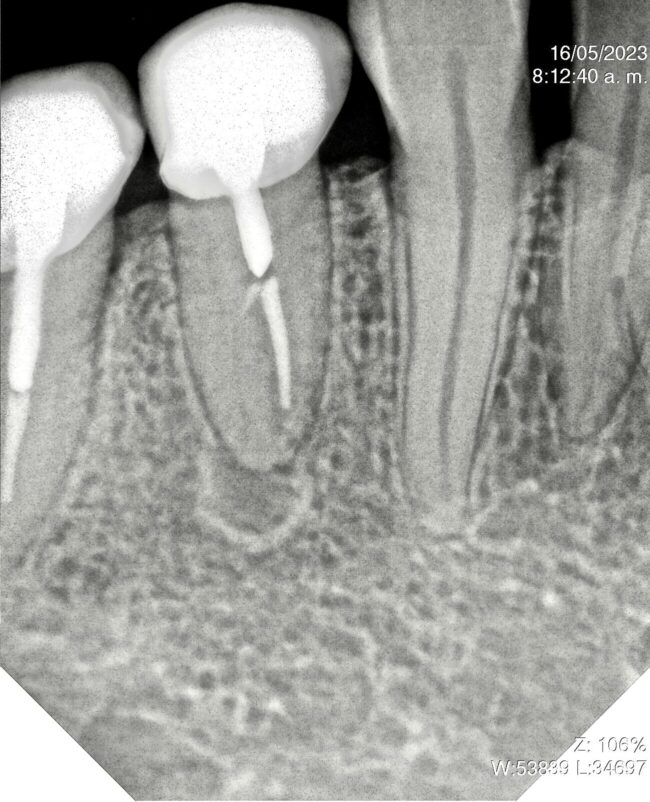

El Dr. Rubén Monge nos muestra en este caso un paciente con absceso apical severo en 1.6 con un tratamiento de conducto realizado previamente. En el retratamiento utiliza RetreatAll® para eliminar la gutapercha y BlueShaper® para la instrumentación.